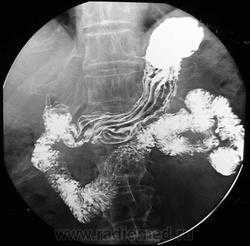

Ирригоскопия по-прежнему является одним из важнейших методов исследования всех отделов толстой кишки. Она дополняет данные колоноскопии и позволяет получить более полную информацию о состоянии органа. Одно из самых частых показаний к ирригоскопии – диагностика рака толстой кишки, полипов и дивертикулов. При ирригоскопии рак толстой кишки виден как дефект наполнения с четкой границей между неизмененной слизистой оболочкой и опухолью; выявляются признаки ригидности кишечной стенки. Нередко участок опухолевого поражения вызывает циркулярное сужение просвета кишки (симптом «яблочного огрызка»). Рентгенологические проявления рака толстой кишки зависят от гистологической формы опухоли, локализации и степени ее распространения. МСКТ и в особенности методика КТ-колонографии могут служить альтернативой ирригоскопии в скрининге и диагностике рака толстой кишки. КТ позволяет лучше видеть изменения кишечной стенки и стадировать заболевание.